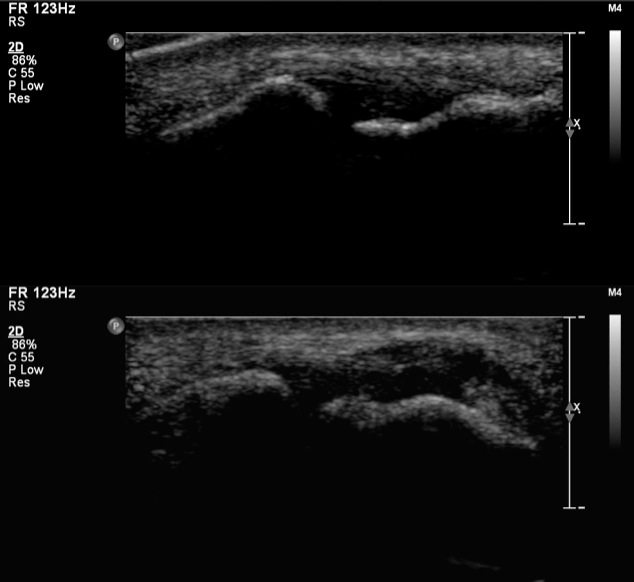

Figure 2 for case Radial collateral ligament ( RID2416 ) tear

Figure 2